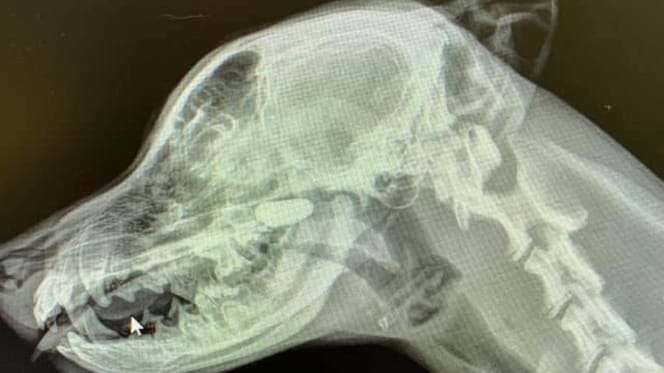

X-ray of a dog's head

The X-ray left everyone speechless

The vet continued her investigation and ordered X-rays of the young dog. First, she examined his chest, but Sarah couldn't spot anything suspicious on the film. She then requested a profile X-ray of his head and neck. And this time, she found what she was looking for!

There, in the nasal passages, was a clearly visible foreign object that definitely shouldn't have been there. It turned out to be a small stone that the puppy had somehow managed to get lodged up his nose. Once it was removed, the little Labrador felt much better immediately.